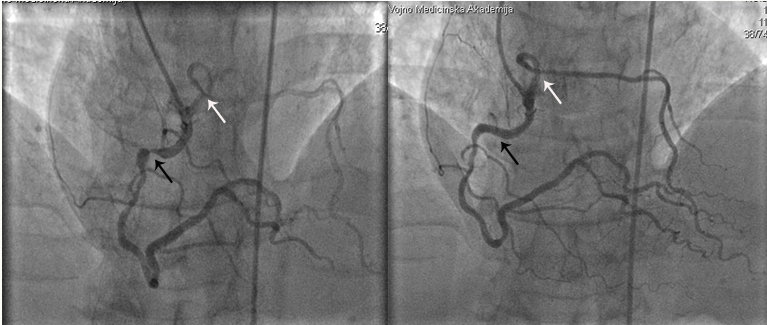

Abstract PDF ECG 1 Angio 1 Angio 2 Angio 3 Angio 4 ECG 2 Table Chart Original File 1 2 3 4 5 6 Reply to reviewer Fig. 1. ECG during myocardial infarction Fig. 2. Coronary angiography of LCA during myocardial infarction Fig. 3. Coronary angiography of LCA during myocardial infarction Fig. 3a. Coronary angiography of LCA during myocardial infarction Fig. 4. Coronary angiography of LCA 2 years after myocardial infarction Fig. 5. Coronary angiography of LCA 2 years after myocardial infarction Fig. 6. ECG 2 years after myocardial infarction Fig. 7. Thrombolytic trials in patients with coronary artery dissection Fig. 8. Flow chart of the study selection process -

Iatrogenic dissection of the left main coronary artery during elective diagnostic procedures – A report on three cases